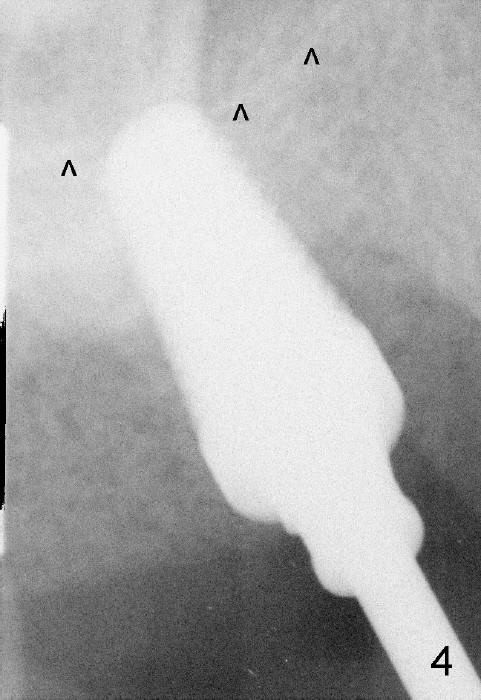

The upper right 1st molar fractures, the lingual portion mobile (Fig.1). There are deep pockets mesiolingually and distolingually. Fig.2 is preop PA, showing mesial bone resorption (*). The 84-year-old lady agrees extraction and immediate implant. Extraction is difficult due to not only root fracture but also hemorrhage. Following debridement of granulation tissue, the 3 sockets are packed with gauze for hemostasis. Even so, there is oozing from the bone. The septum can not be seen clearly. Its position is determined by an explorer. Osteotomes have to be used for osteotomy in the septum, followed by taps. The first intraop PA shows that 5x20 mm tap penetrates the sinus floor (Fig.3 ^). The osteotomy is further enlarged until 7x17 mm tap with stability (Fig.4). So far there has been no sign of sinus membrane perforation. Mixture of freeze dry mineralized bone and Osteogen is placed in the socket and pushed to the buccal and lingual walls as well as into sinus using a 4 mm flat end osteotome. A 7x17 mm implant is initially difficult to be inserted possibly due to blockage by bone graft. The osteotomy have to be recreated by a series of osteotomes and taps before placement of the 7x17 mm implant. It appears that the apical threads have been engaged into the sinus floor for primary stability (Fig.5). The insertion torque is 40 Ncm. According to our experience (1,2), this is not enough; finally the torque is increased to 60 Ncm by turning the implant more apically. The large implant obliterates the socket mesiodistally; the buccal and lingual gaps are filled with bone graft, followed by a collagen membrane (Fig.6 *) and suture. In order to protect the membrane, a short abutment is placed (A) and perio dressing (Fig.7*) is placed without occlusal interference. The abutment is removed 1 month postop, as the perio dressing has been dislodged. The patient returns for restoration 8 month postop. Bone regeneration occurs apparently in the coronal aspect of the implant (Fig.8), especially mesially (*, as compared to Fig.5). The gingiva-level implant is slightly subgingival mesially (Fig.9 M), probably due to high placement (compare to Fig.6). There is no bone resorption 6 months post crown (Fig.10 C) cementation.